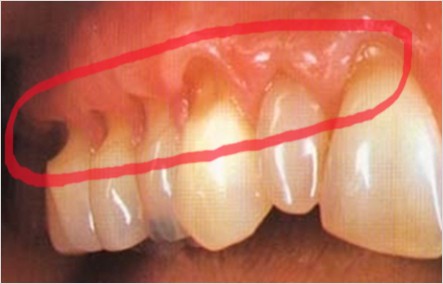

치경부 마모증은 치아의 목 부분, 즉 치경부에 해당하는 치아와 잇몸이 만나는 경계 부위가 V자 모양으로 패이면서 발생하는 현상입니다. 이로 인해 치아가 시리고, 차가운 음식이나 음료를 섭취할 때 통증을 느낄 수 있습니다. 마모된 부위가 점점 더 커지게 되면 충치나 치아 파절 등 다양한 문제로 이어질 수 있어 조기 치료가 중요합니다.

치경부 마모증은 강한 양치질, 질긴 음식, 산성 음료 등 다양한 요인으로 인해 발생할 수 있습니다. 다음에서 이 세 가지 주요 원인에 대해 더 자세히 살펴보겠습니다.